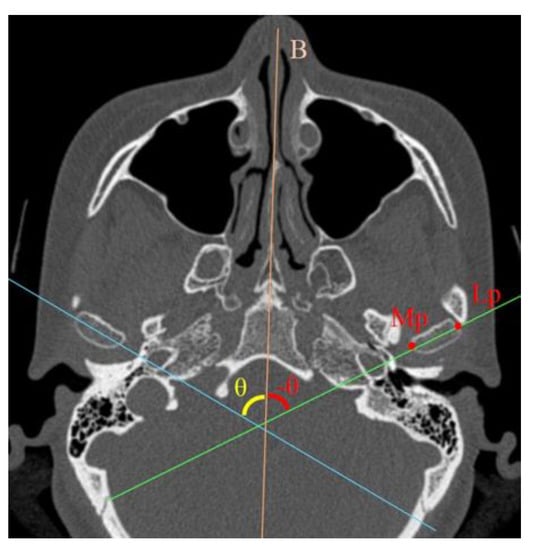

2.2.2. Three-Dimensional Computed Tomography (3D CT) Analysis

| X | Y | Z | θ | X | Y | Z | θ | |||||||||

| Mean | SD | Mean | SD | Mean | SD | Mean | SD | Mean | SD | Mean | SD | Mean | SD | Mean | SD | |

| Lp (mm) | −0.1 | 0.4 | 0.1 | 0.1 | 0.1 | 0.5 | −0.2 | 1.3 | 0.2 | 1.0 | 0.4 | 0.7 | ||||

| Cp (mm) | −0.1 | 0.4 | 0.1 | 0.5 | 0.2 | 0.6 | −0.7 | 2.3 | 0.1 | 2.5 | −0.2 | 0.9 | ||||

| An (mm) | 0.1 | 0.8 | −0.6 | 3.4 | −0.5 | 2.3 | −0.9 | 2.8 | 2.4 | 2.2 | −1.9 | 4.0 | ||||

| Condylar angle (°) | 3.0 | 1.1 | 3.0 | 3.9 | ||||||||||||